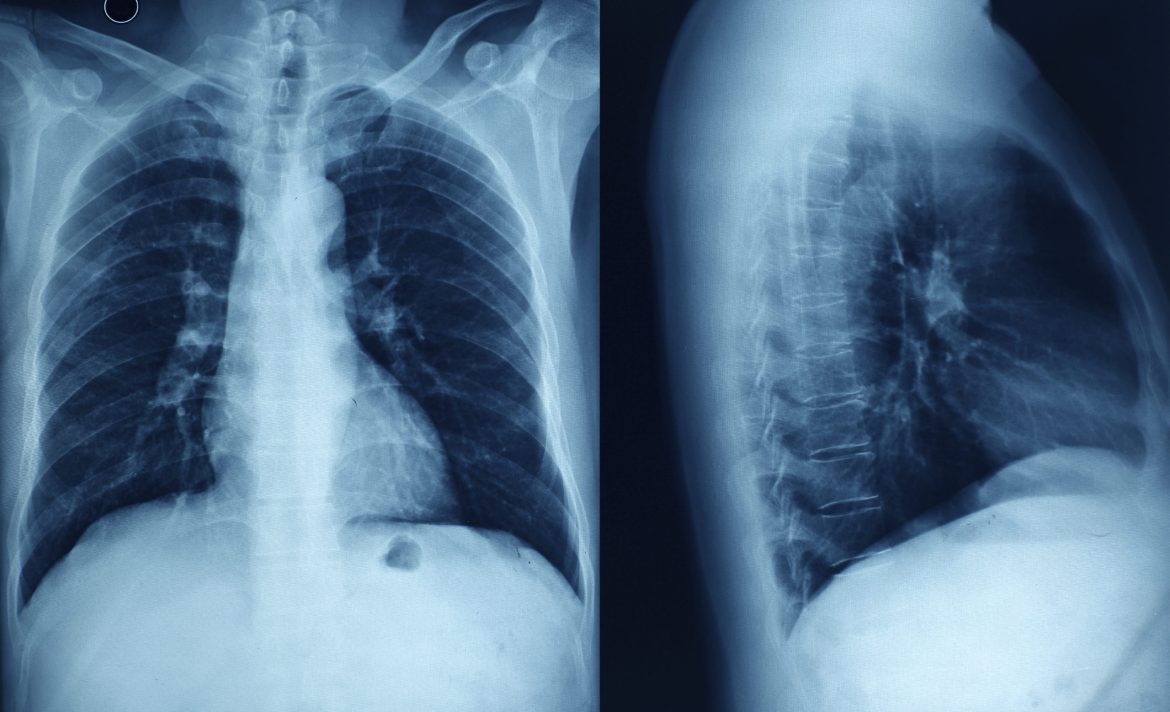

While chest X-rays are routinely performed in patients with suspected cardiac pathology, their utility in diagnosing myocarditis is limited:

Imaging Features: Chest X-rays may show nonspecific findings such as cardiomegaly (enlarged heart), pulmonary congestion (evidence of fluid overload), or pleural effusions (fluid around the lungs), which can be secondary to heart failure but are not specific to myocarditis.

Sensitivity and Specificity: Chest X-rays lack sensitivity and specificity for detecting myocarditis directly. They may provide supportive evidence in the context of clinical suspicion and can help assess for complications such as pulmonary edema or effusions.

Role of Chest X-rays

In clinical practice, chest X-rays are typically part of the initial evaluation in patients presenting with cardiac symptoms or signs of heart failure:

Detection of Complications: Chest X-rays can identify complications such as pulmonary congestion or pleural effusions, which may occur secondary to myocarditis-induced heart failure.

Supportive Evidence: While chest X-rays do not directly visualize myocardial inflammation, they can provide indirect evidence of cardiac involvement and guide further diagnostic steps.

Consider the following scenarios where chest X-rays may play a role in the diagnostic pathway of myocarditis:

Case 1: A young adult presents with chest pain, fever, and elevated cardiac biomarkers. Chest X-ray reveals cardiomegaly and pulmonary congestion, prompting further evaluation with echocardiography and cardiac MRI.

Case 2: An elderly patient with known coronary artery disease presents with worsening heart failure symptoms. Chest X-ray shows bilateral pleural effusions and signs of pulmonary edema. Clinical suspicion for myocarditis arises, leading to comprehensive imaging and laboratory workup.